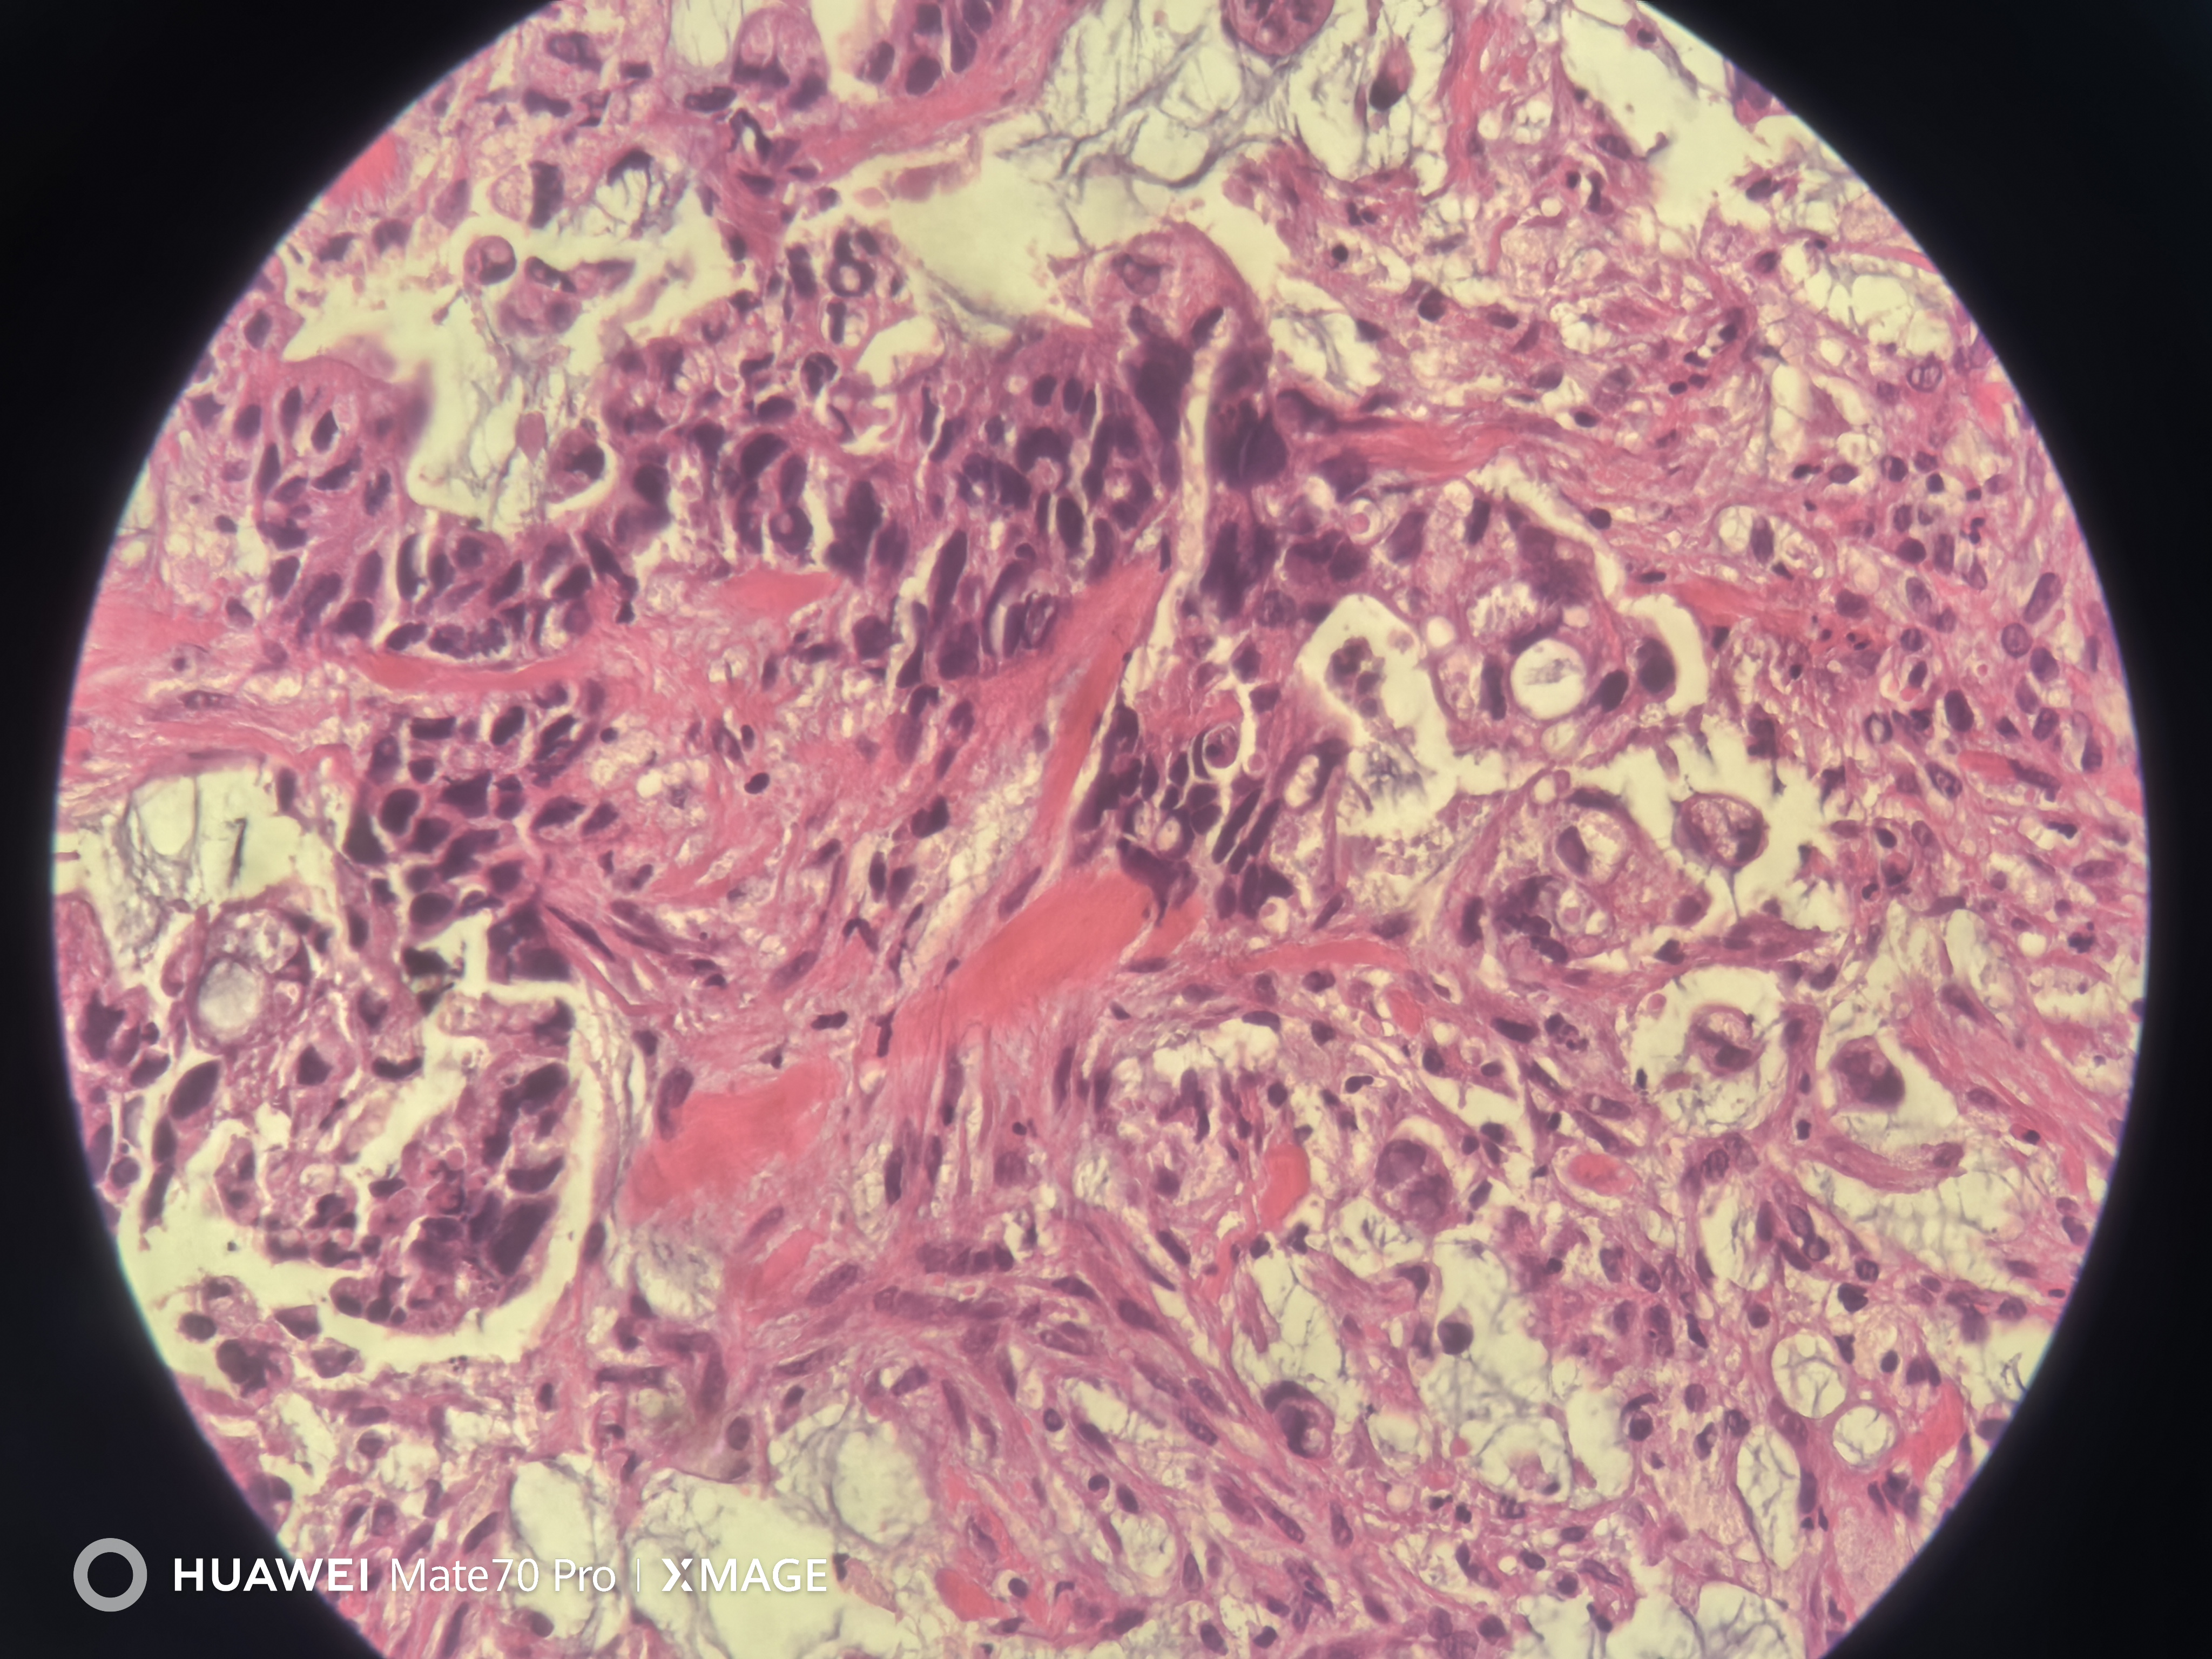

急!请老师帮忙看看

性别

男

年龄

78岁

临床诊断

结肠CA

一般病史

横结肠近肝曲不规则增生性肿物,环周生长,管腔狭窄,无法继续进境,表面充血糜烂坏死,质脆,易出血

标本名称

肠镜活检

大体所见

送检组织0.15x0.1x0.1厘米~0.2x0.1x0.1厘米

结肠腺癌

腺癌

(横结肠肿物活检)腺癌。